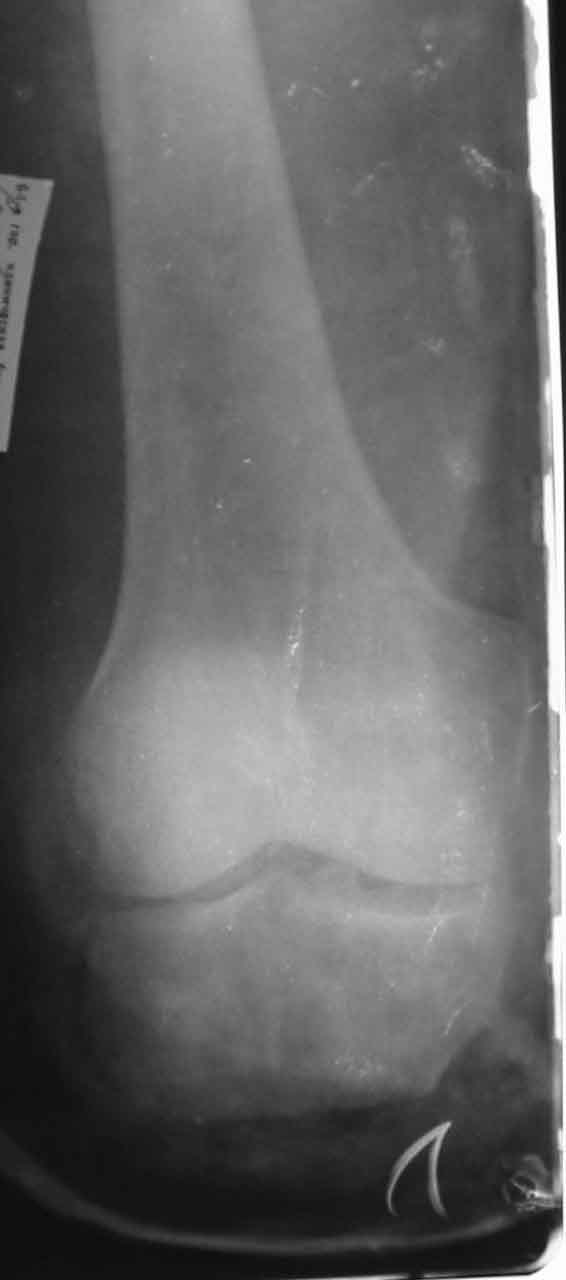

Больной С., 50 лет, строитель, поступил в 64 ГКБ 17.05.02., доставлен СП.Травма за 1 час до поступления на работе на ноги пострадавшего наехал трактор. При поступлении больного тяжелое, сознание спутаное, больной возбужден, не критичен. Кровотечения нет. Кожные покровы бледные. Пульсация на периферических артериях слабо определяется. АД 80/60 мм рт ст. Справа закрытый перелом большельшеберцовой без смещения.На Р-граммах левой голени многооскольчавый перелом костей с/3 в/3 голени (см 1)). Другие сегменты не пострадали.ДЗ. Открытый Многооскольчатый раздробленный перелом костей левой голени. Разможжениемягких тканей левой голени. Закрытый перелом с/3 большеберцовой кости правой голени со смещением. Вывих головки малоберцовой кости. Травматический шок 2-3 ст. Минуя приемное отделение больной поднят в экстренную операционную. После выведения больного из шока выполнена ПХО, и учитывая разможжение мягких тканей левой голени и многооскольчатый характер перелома - ампутация левой голени на границе в/3, экзартикуляция м/берцовой. Решено было максимально сохранить длину конечности. Ранане ушивалась, наложены провизорные швы (см 2, 3).На правую голень фиксирована разрезной гипсовой повязкой.Производились перевязки Н2 О2 , повязки с левомеколем, по мере спадения отека дозировано подтягивались провизорные швы. По состоянию на 24.05.02 Состояние больного удовлетворительное, субфибрильная лихорадка.Местно: в рану выстоят опил б/берцовой кости, кожный лоскут "болеет", некроз мышц иподкожной клетчатки в наружном углу раны (см 4).Вопросы:-Оправдана ли сберегательная тактика при поступлении?-В последующем имеет ли смысл постараться сберечь максимально возможную длинусегмента? -Если да то как заместить дефект тканей?-Если нет то какой вид ампутации выбрать и на каком уровне?Глеб КоробушкинАспирант Кафедры травматологии и ортопедии РГМУ, Москва

27.05.02. Выполнена Некректомия, вторичная хирургическая обработка раны

швы. При ревизии раны выявлено рана по передне-нижней поверхности культи левой голени, в рану выстоит опил большеберцовой кости, рана 17х7 см